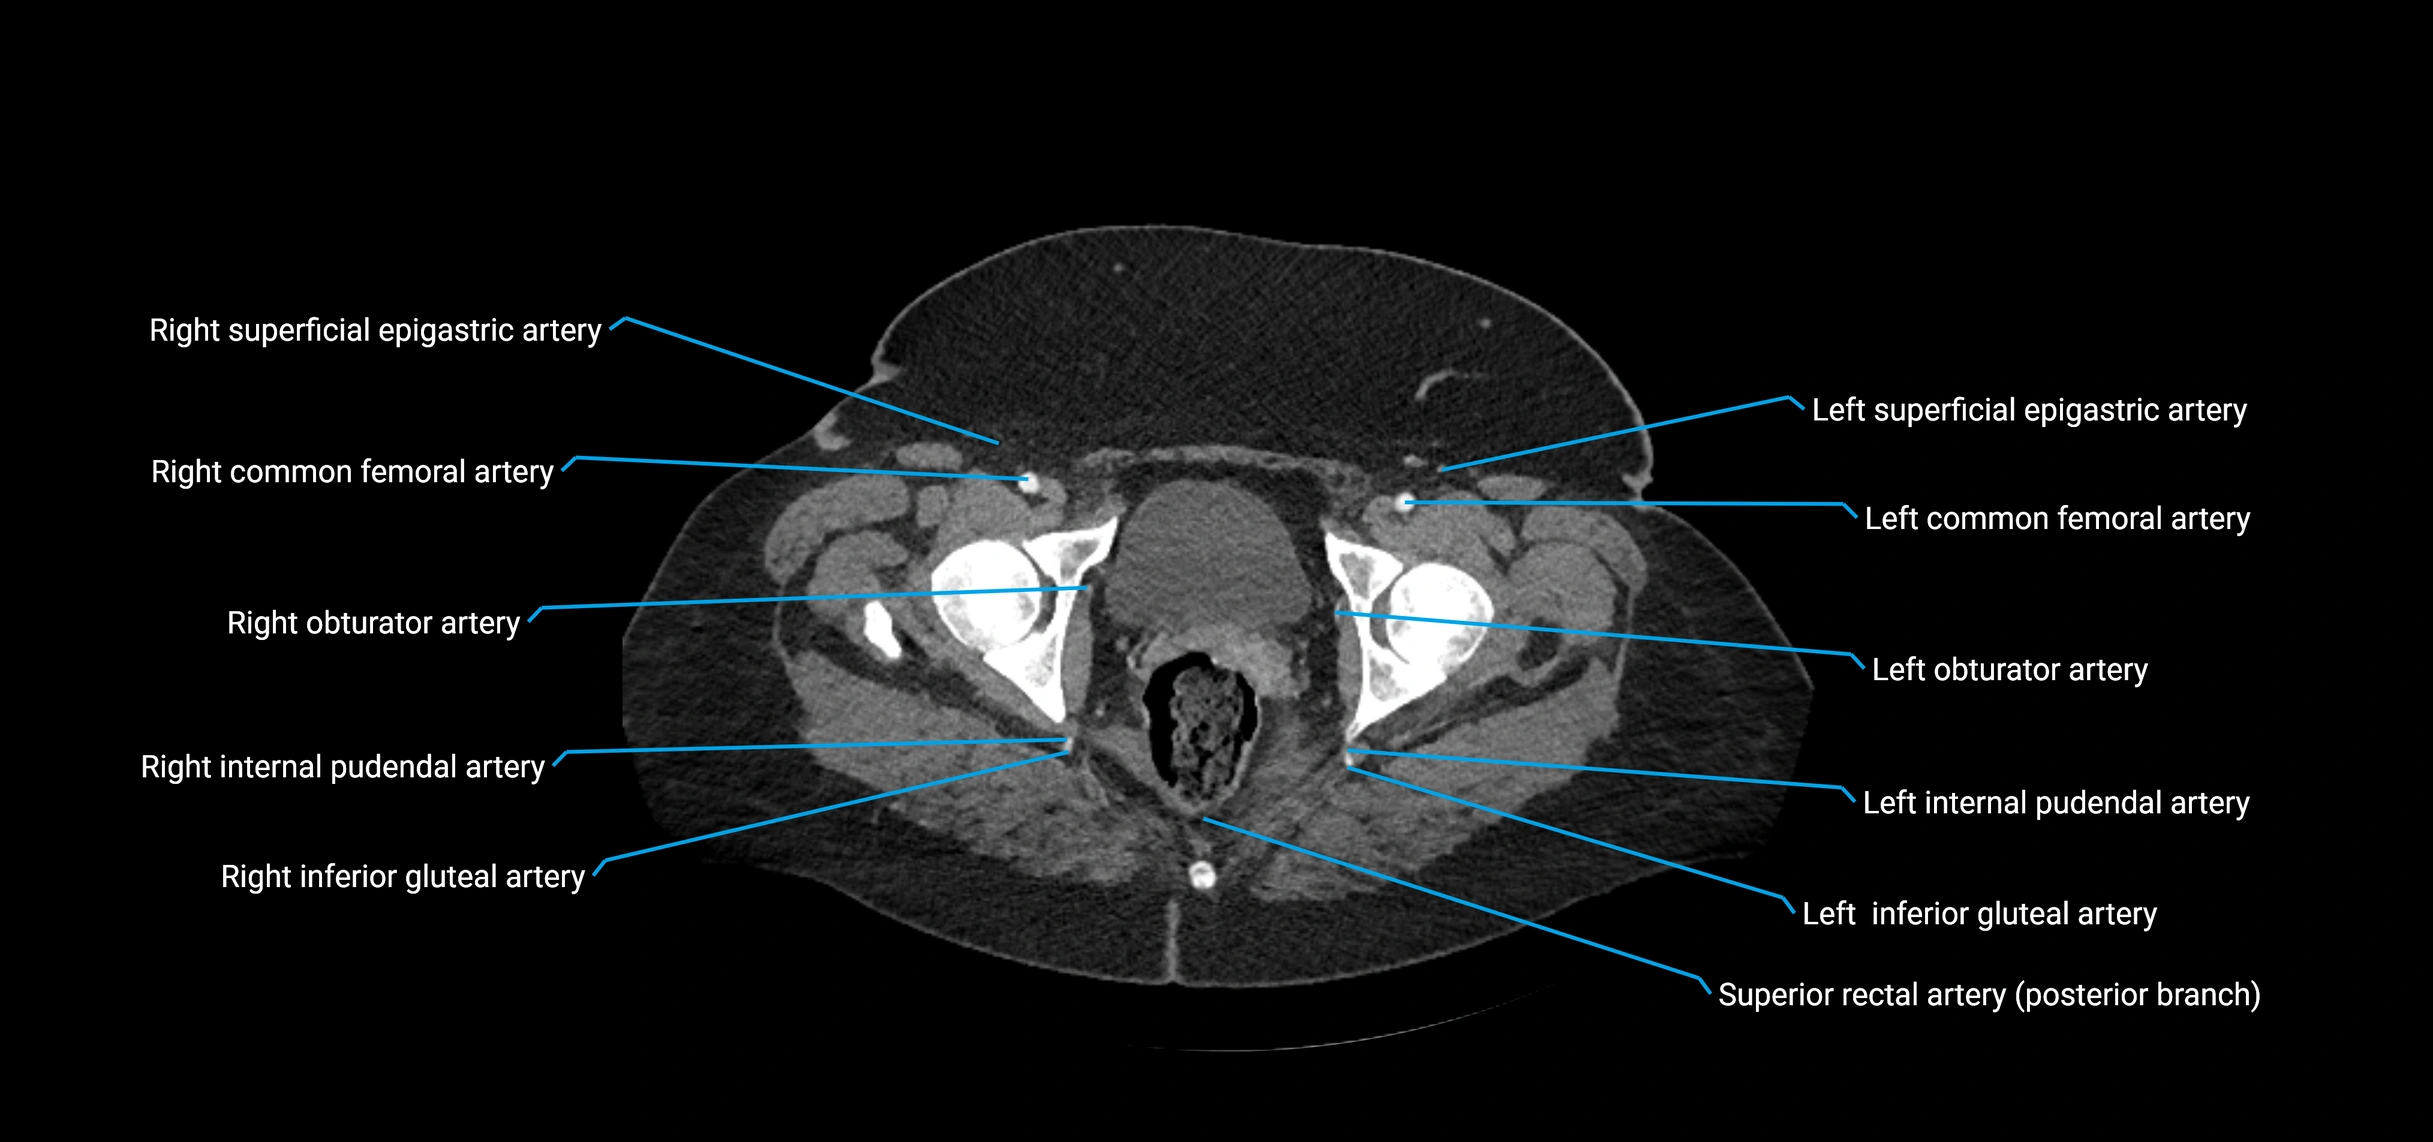

CT images

image

Contrast-enhanced CT (CTA):

• Gold standard for abdominal aortic imaging

• Provides excellent detail of lumen, wall, aneurysm, thrombus, and branch vessels

• Multiplanar and 3D reconstructions help in aneurysm measurement, stent graft planning, and dissection evaluation